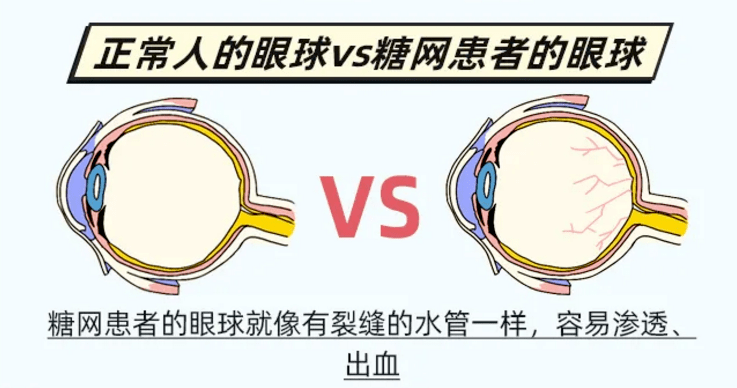

怎么才能避免中招?不是夸张,糖尿病性眼病就像"温水煮青蛙",很多人一开始都没什么感觉,等到眼睛看不见后,才想到要去看眼科,那时可能就晚了!所以,糖尿病患者定期去医院检查眼睛真的很重要!

早发现、早治疗是最好的预防方法,还要注意控制血糖!平时要——控制血压、血脂 戒烟戒酒 调整合理饮食 适量运动 注意休息。最后再提醒一下,高糖饮料,尽量就别喝了。